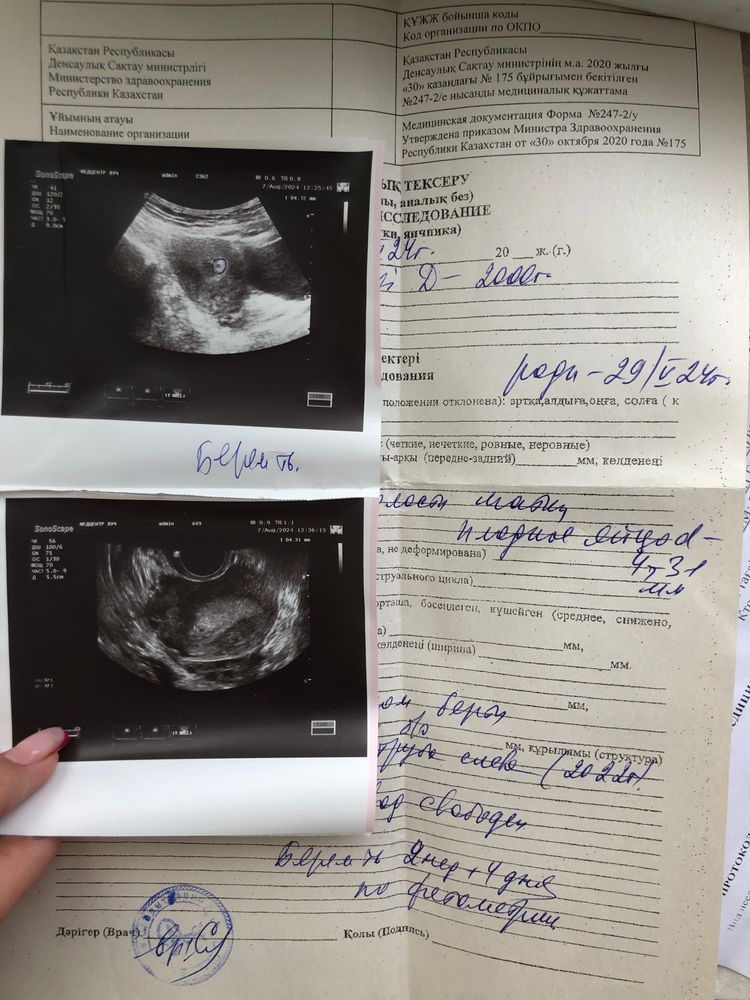

Тома, это я 7го сделала узи там и так и вагинальна тоже посмотрела Изображение ….. Это сделали 16го были кровяные выделения тогда сказали срок очень мал сердцебиение невозможно услышать сказали нужно подаждать

Диана Есенгелди, это 16 го августа Изображение

Диана Есенгелди, так это не плодное яйцо,у вас первое узи 7 числа якобы пя 4 мм,а через 9 дней 3 мм, это включение не растет,а плодное яйцо растет по 1 мм в сутки,если б это было плодное яйцо то с 4 мм за 9 дней оно выросло было до 13 мм и был в нем желточный мешочек,а у вас просто какое-то включение схожее на плодное яйцо которое не растет да и тесты отрицательные,100% не беременность это